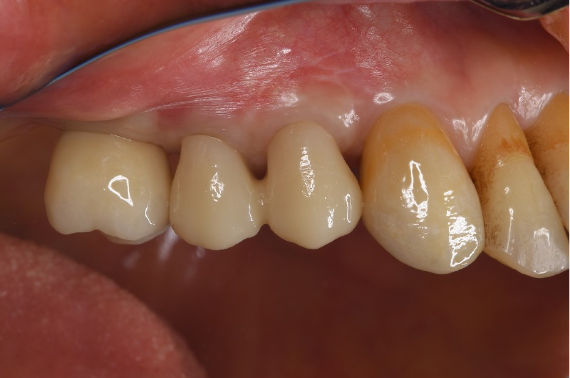

症例3

| 項目 | 詳細 |

|---|---|

| 患者様データ | 50代 男性 |

| 来院時の主訴 | 「左下で噛むと違和感がある。」 |

| 医院の診断 | 左下第二大臼歯の歯根破折 |

| 通院期間 | 9か月 |

| 来院回数 | 12回 |

| 治療費 | 総額:835,000円(税抜) 【内訳】 インプラント埋入手術250,000円、GBR(骨再生手術)150,000円、2次手術+FGG(遊離歯肉移植術)55,000+60,000円、仮歯30,000円、インプラント上部構造(セラミッククラウン)170,000円、隣在歯セラミッククラウンのやりかえ120,000円 |

| リスクと副作用 | 定期的なメンテナンスが必要、術後若干の腫れと痛み |

| ここがこだわりのポイント!☝ | インプラント周囲に角化歯肉と言われる健常な歯肉がなかったので、口蓋からの歯肉移植を行っています💡この角化歯肉がないと、インプラントをしてもうまく歯磨きができないことがあります。 |